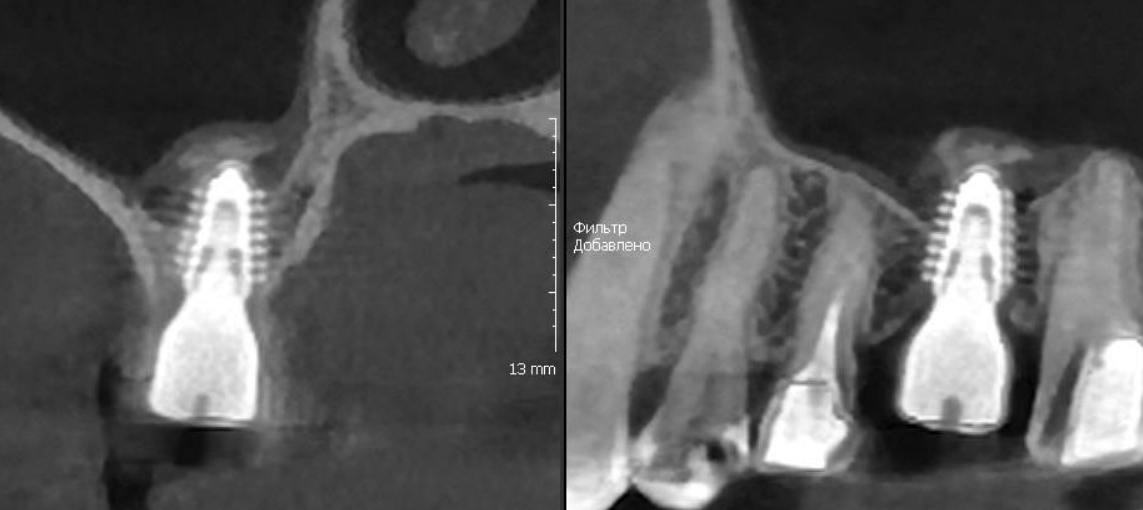

Закрытый синус-лифтинг, выполненный вогнутым остеотомом, с показательным срезом КТ после операции.

Виден смещенный фрагмент кости и Шнейдерова мембрана, которая была без повреждений поднята вслед за костью.